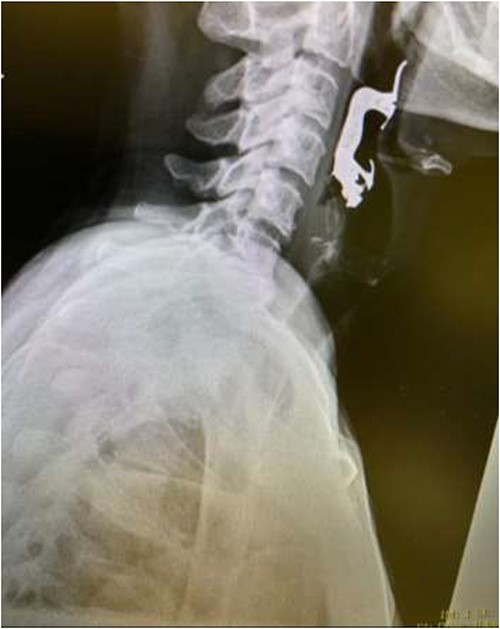

The first case is of a 7-year-old child presenting with a history of barbed wire inhalation. X-ray imaging of his neck and chest showed a radio-opaque object visible in the upper airway with sharp edges (Figs 1 and 2). Due to the position of the foreign body, endotracheal intubation was not feasible. A trial of apnoeic oxygenation using high-flow nasal oxygenation was used as an alternative, and this allowed for an unobstructed view of the larynx, facilitating the safe removal of the foreign body (Fig. 3).

AP chest radiograph showing the sharp-edged radio-opaque object.